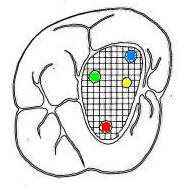

Cuarto conducto en molares superiores (Color amarillo conducto mesio-palatino)

La raíz mesiovestibular es achatada en sentido mesiodistal y amplia en sentido vestibulopalatino.El conducto mesiovestibular con frecuencia es curvo y de sección en forma de hendidura. La existencia de dos conductos en esta raíz, puede presentar la siguiente configuración:

• uno vestibular (Color azul)

• y el otro palatino (Color amarillo)

La raíz distovestibular tiene dimensiones menores que la mesiovestibular y no presenta curvaturas acentuadas. El conducto distovestibular (Color verde) por lo general es atrésico y puede presentar curvaturas.

La raíz palatina es la más voluminosa de forma cónica y sección circular. Puede ser recta o curva. Cuando es curva, el sentido e la curva es hacia vestibular. El conducto palatino (Color rojo) es amplio y de fácil acceso, rectilíneo o con una curva leve hacia vestibular.